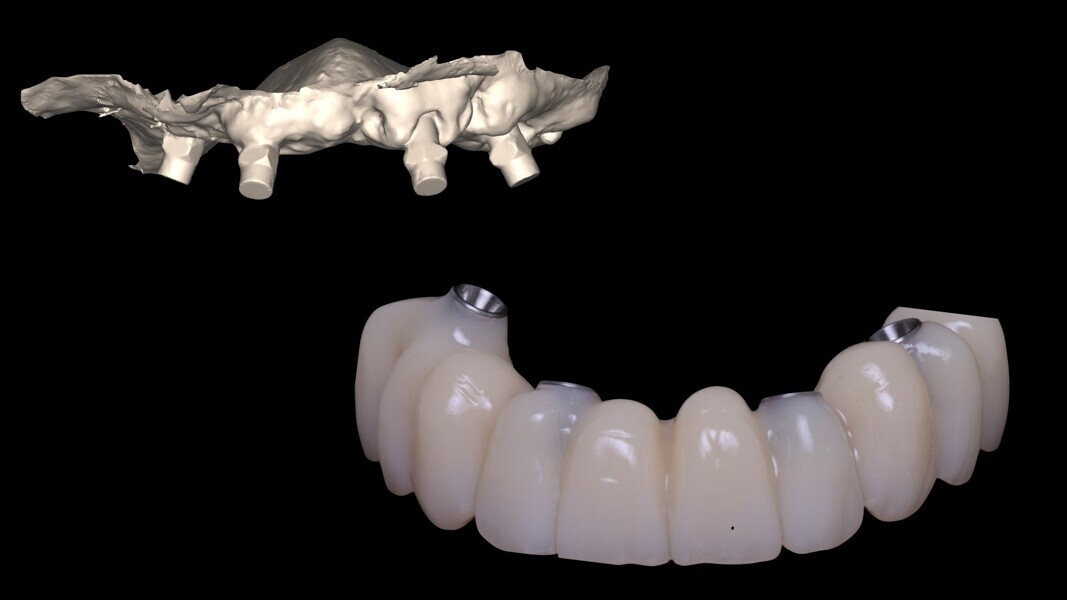

Les deux bridges provisoires sont vissés par l’intermédiaire de vario-bases à la mandibule et au maxillaire (Fig. 16). Nous réhabilitons le patient grâce à la réalisation d’un bridge full zircone à connexion directe sur multi-unit au maxillaire.

À la mandibule un bridge PMMA sur vario-base est vissé. Nous n’optons pas pour la réalisation de deux bridges full zircone, pour des questions de dureté de matériaux et de confort pour le patient. Nous combinons l’esthétique d’un bridge full zircone au maxillaire et la souplesse du PMMA à la mandibule (Fig. 17). La photo avant-après du patient, illustrant son état au premier jour et à la fin de son traitement, est présentée sur la figure 18.